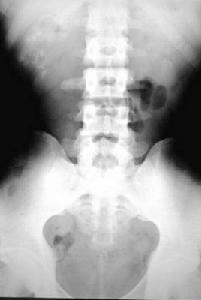

(1)尿路X線平片:腎小盞外側乳頭部腎髓質內顯示大小不等數目不定的小結石,多為粟粒狀,呈多發性、簇狀或放射狀排列。其他檢查如腹部X線平片可見兩側腎臟體積大小改變明顯,且有囊腫樣或鈣化陰影

(2)靜脈尿路造影:腎錐體及小盞周圍可見被造影劑充盈的梭形小囊腫多數囊腫排列成扇形式葡萄串樣或花束樣;腎小盞增寬,杯口擴大。

(3)逆行腎盂造影:顯示腎盞杯口擴大。